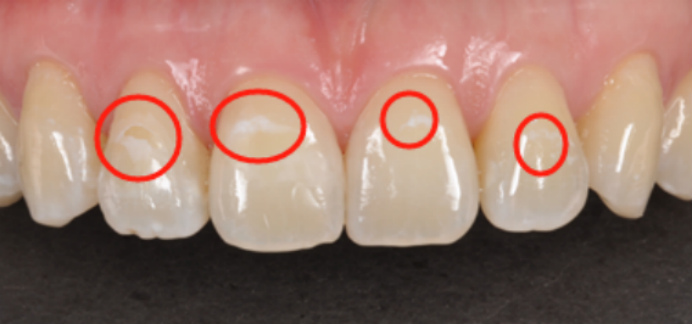

1. 兒童牙齒表面出現白色粉筆樣斑塊、牙齒窩溝或鄰面發黑、牙齒缺損或小洞;

刷凈牙齒后觀察,發現白斑或手感粗糙。這可能就是脫礦了,需要注意護理或看口腔醫生!

△ 白色粉筆樣斑塊